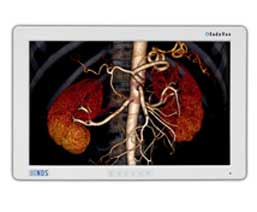

GTI Groups offers permanent solutions in medical industry and we only work with the global leaders in designing and manufacturing comprehensive radiology and medical imaging and informatics solutions for today’s operative process. Our partners’ market leadership is built upon their unique ability to supply the medical profession with technologies that enable practitioners to integrate information from many sources, visualize a defect or condition within the body and to perform an intervention that improves the quality of care. They dominate today’s surgical markets and are considered the industry standards for the digital world. So we always feel a little bit lucky for finding out the right partners and right products.

Our Medical Imaging Professional Services provides a range of services and analytical tools to supplement our solutions and are designed to help you and your organization realize the full value of medical imaging in your facilities. RIS (radiology information) and CVIS (cardiovascular imaging systems) are designed to help health care organizations of all sizes and complexity manage the massive amount of specialized imaging applications that come from dealing with today’s medical imaging departments. According to the Medical Imaging Monitors, we are pretty experienced and have a great knowledge upon the industry. Our business partners are as follows: